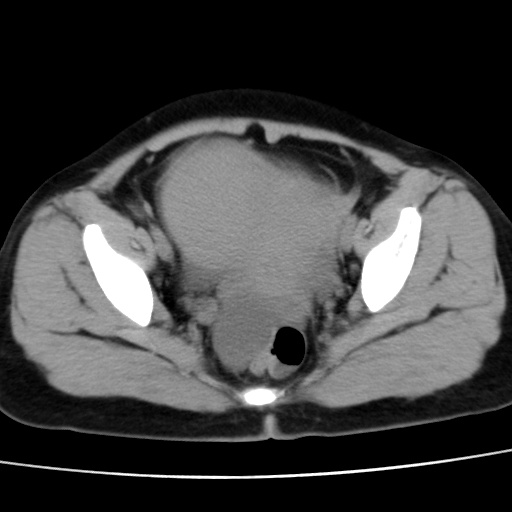

子宫多发肌瘤吗

多发性子宫肌瘤.

考虑多发子宫肌瘤,子宫直肠窝双囊性占位,另直肠周围脂肪密度增高,不知有何病史

支持考虑多发子宫肌瘤~!子宫直肠陷凹积液?

支持考虑多发子宫肌瘤~!子宫直肠陷凹积液!

子宫肌瘤,宫体部后方见液性密度影,是肠道还是子宫与直肠陷窝积液不好说,我觉得它的位置有点高

支持考虑多发子宫肌瘤!子宫直肠陷凹积液!

患者发热,而子宫直肠窝液性灶有明显边缘且局限且囊性,不除外为包裹性积液或脓肿

支持考虑多发子宫肌瘤,子宫直肠陷凹积液可能。

考虑多发子宫肌瘤

1)考虑子宫肌瘤可能性大。2)子宫后方囊性占位性病变,不排除卵巢囊肿可能。

考虑多发子宫肌瘤。子宫后方囊性占位性病变,不排除卵巢囊肿可能。